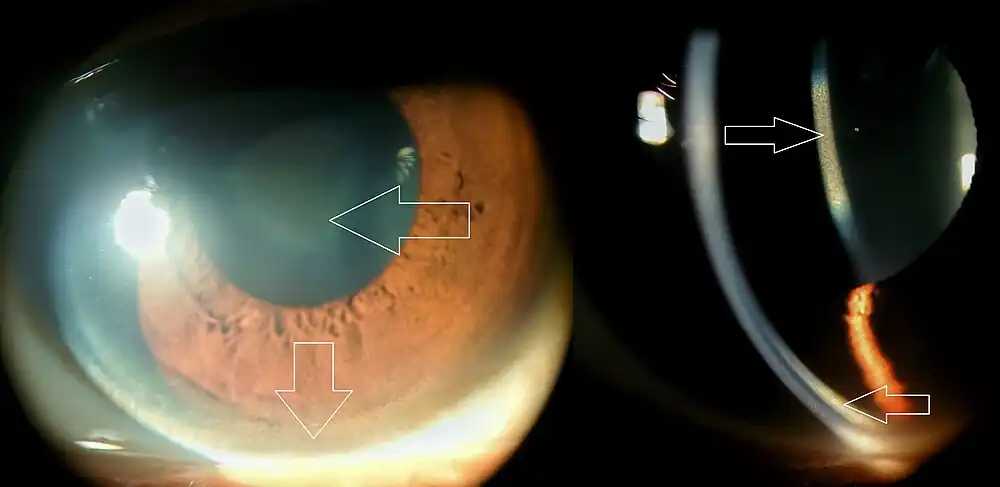

| A Kayser–Fleischer ring in a 32-year-old patient who had longstanding speech difficulties and tremor. | |

Kayser–Fleischer rings (KF rings) are dark rings that appear to encircle the cornea of the eye. They are due to copper deposition in the Descemet's membrane as a result of particular liver diseases.[1] They are named after German ophthalmologists Bernhard Kayser and Bruno Fleischer who first described them in 1902 and 1903.[2][3][4] Initially thought to be due to the accumulation of silver, they were first demonstrated to contain copper in 1934.[5]

The rings, which consist of copper deposits where the cornea meets the sclera, in Descemet's membrane, first appear as a crescent at the top of the cornea. Eventually, a second crescent forms below, at the "six o'clock position", and ultimately completely encircles the cornea.[1][6]

As Kayser–Fleischer rings do not cause any symptoms, it is common for them to be identified during investigations for other medical conditions. In certain situations, they are actively sought; in that case, the early stages may be detected by slit lamp examination before they become visible to the naked eye.[1]